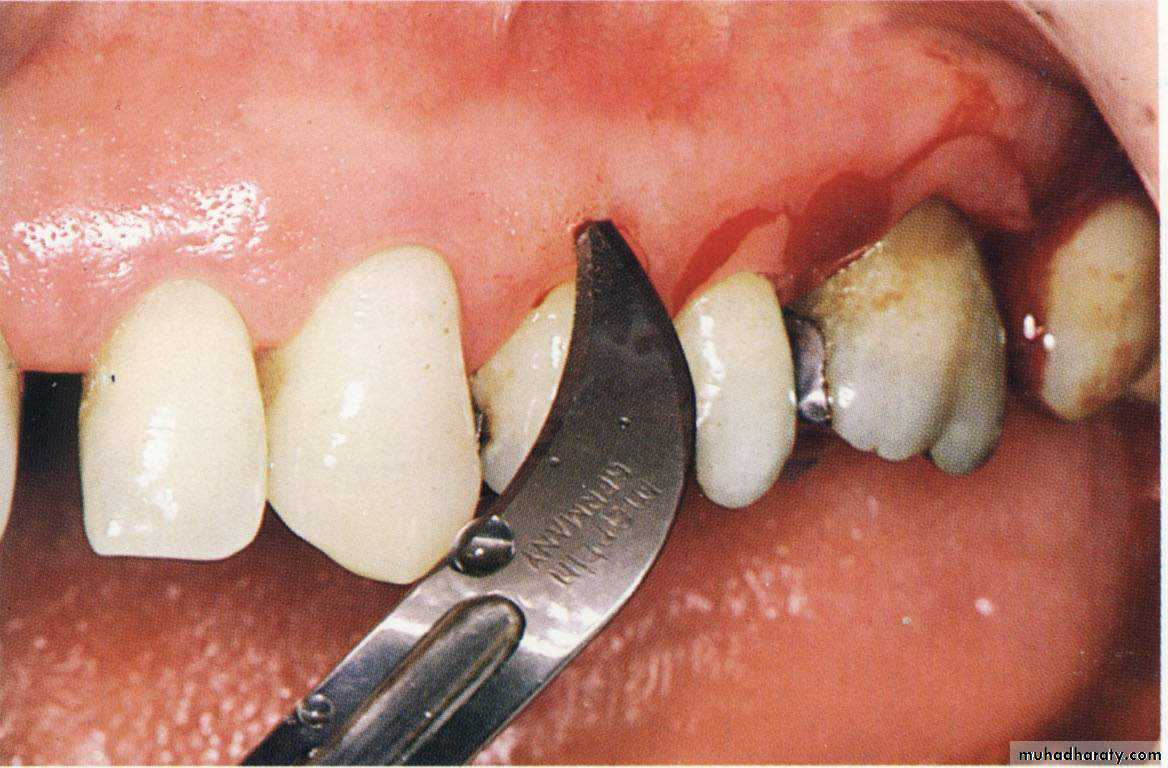

Primary beveled incision, which carried out according to the bleeding points.

Reversed bevel incision: opposite to the gingivectomy incision.

1st incision 1º incision Reverse bevel incision11 or 15 surgical scalpel used

Starts at a distance from the gingival margin aiming at the bone crest.